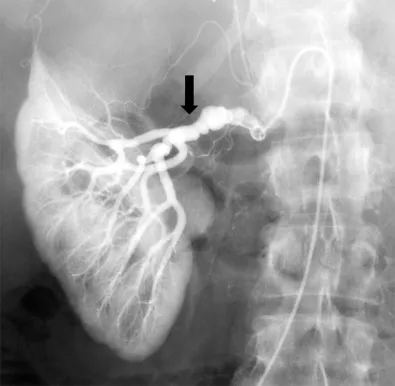

Cálculos de ácido úrico — o que fazer nos casos refratários?

Urolitíase por ácido úrico tem como alvo central o pH urinário, mas nos refratários o manejo exige titulação cuidadosa de alcali, adesão rígida e, se preciso, xantino-oxidase. ⚖️ Escolher entre citrato-K e bicarbonato de sódio depende do perfil clínico e dos riscos associados. 👉 Quando a alcalinização não basta, o nefrologista precisa seguir um roteiro sistemático para evitar recorrência.